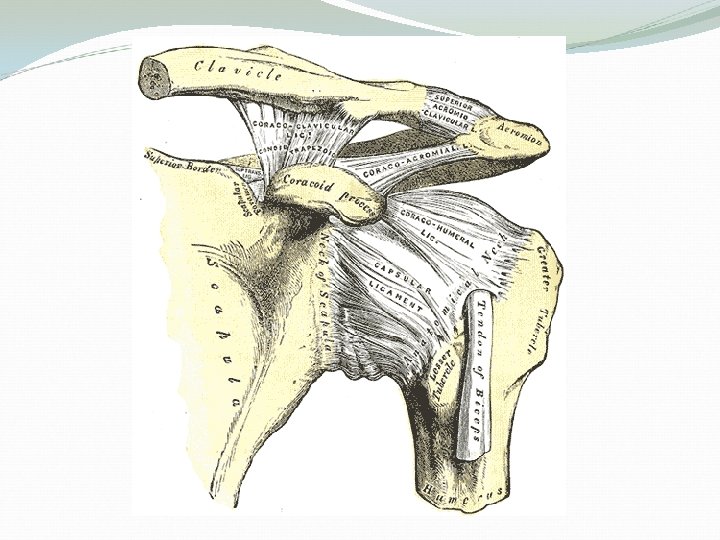

Joints Glenohumeral joint: the main joint Acromioclavicular (AC) joint Sternoclavicular (SC) joint Scapulothoracic joint

Acromioclavicular Pathology The AC joint is different from joints like the knee or ankle, because it doesn't need to move very much. The AC joint only needs to be flexible enough for the shoulder to move freely. The AC joint just shifts a bit as the shoulder moves.

The joint is stabilized by three ligaments